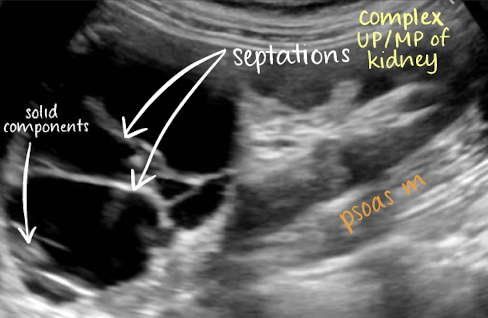

??

complex cyst

has septations and solid components